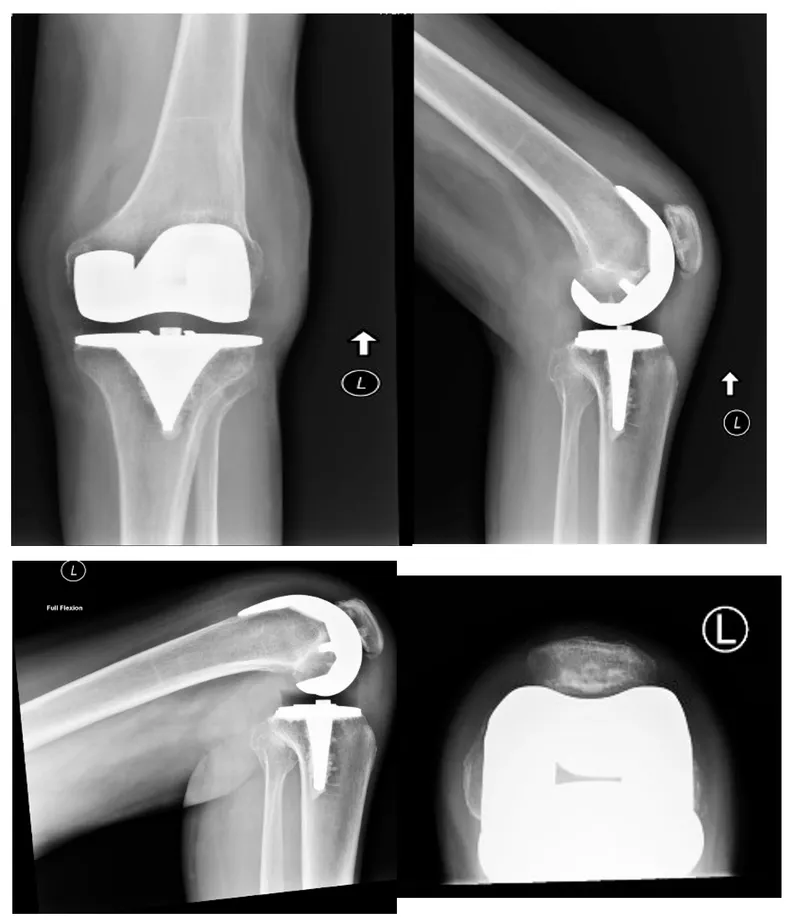

- Essential X-rays: AP, Lateral, Skyline views.

- Long leg films (scanogram): Crucial for mechanical axis & deformity assessment.

- Templating: Component sizing, alignment, bone resection levels.